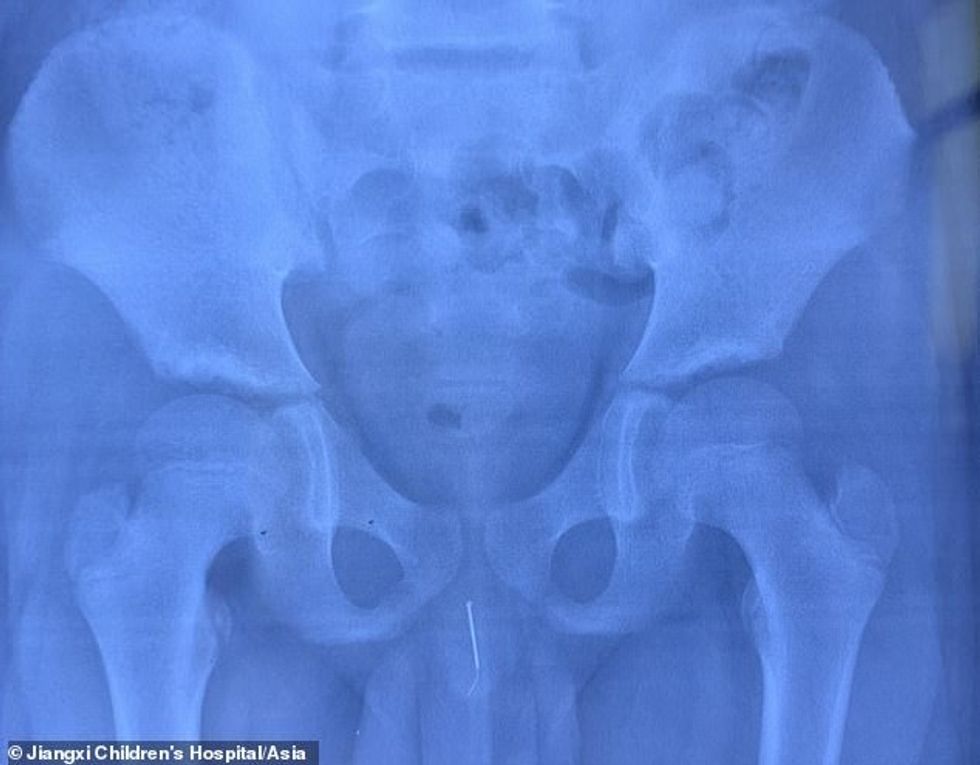

Në pamundësi për të shpjeguar dhimbjen e djalit, ai u dërgua në Spitalin e Fëmijëve Jiangxi në provincën Jiangxi në pjesën qendrore të Kinëa për një radiografi, transmeton Telegrafi.

Pas skenimit, doktorët u tronditën kur panë se një gjilpërë 8 centimetërshe ishte futur në penisin e tij dhe pastaj kishte shkuar deri në tubin e tij të fshikëzës, shkruan Daily Mail.